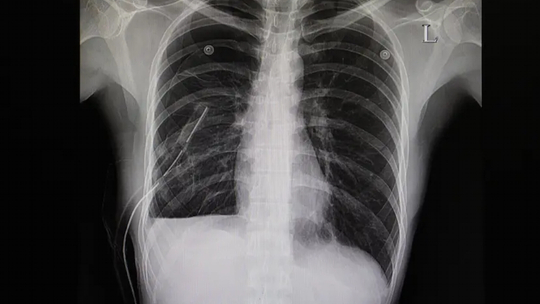

Pemeriksaan radiologi foto polos toraks on site dilakukan di IGD, dan hasil yang didapat adalah gambaran pneumothorax di sisi paru-paru kanan, dengan ukuran sekitar 28%. Bercak infiltrat diffuse pada lapangan paru-paru bilateral, terutama lapangan atas kedua paru-paru. Efusi pleura bilateral. Tidak tampak kelainan pada jantung saat ini.

Gambar 1. Foto polos toraks menunjukkan adanya gambaran pneumothorax di sisi kanan paru-paru.